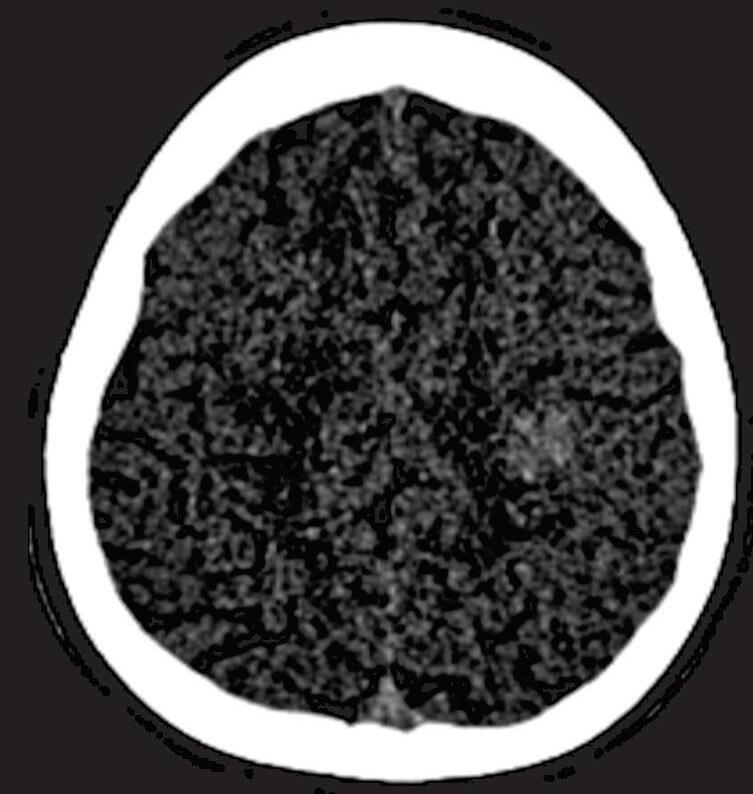

A suspeita diagnóstica das MAVs geralmente é feita por meio de métodos não invasivos de aquisição de imagem, tais como tomografia computadorizada (TC), angiotomografia, ressonância magnética (RNM) e angiorressonância, contudo, as informações anatômicas vasculares necessárias para o planejamento e a execução terapêutica demandam geralmente do estudo dinâmico da angioarquitetura da MAV pela arteriografia cerebral, considerado o exame padrão-ouro para o diagnóstico (Figs. 1-21 e 1-22).35

Em virtude de as manifestações clínicas não serem exclusivas das MAVs, a tomografia computadorizada do crânio sem contraste

é geralmente o primeiro exame realizado na investigação diagnóstica. Algumas alterações presentes nessa tomografia, associadas à história clínica do paciente podem direcionar a suspeição diagnóstica; são eles: pacientes jovens com hemorragia intraparenquimatosa lobar espontânea, sangramento inexplicável intraventricular ou subaracnóideo, presença de calcificações curvilíneas ou salpicadas, ou imagens serpiginosas espontaneamente hiperdensas, que podem corresponder a vasos anômalos integrantes do nidus, a veias de drenagem ou a artérias nutridoras dilatadas. Embora a angiotomografia possibilite uma melhor visualização das estruturas vasculares, a ressonância magnética em contrapartida, permite melhor

Fig. 1-21. TC de crânio sem contraste em cortes (a) axial e (b) coronal. (c) RNM encéfalo T1 com contraste axial. (d) Angiorressonância arterial sagital. Arteriografia digital em (e) AP e (f) perfil, demonstrando MAV não rota localizada no giro pré-central à esquerda nutrida por ramos da artéria cerebral média e caloso marginal esquerdo. Setas azuis apontando para o nidus da MAV.